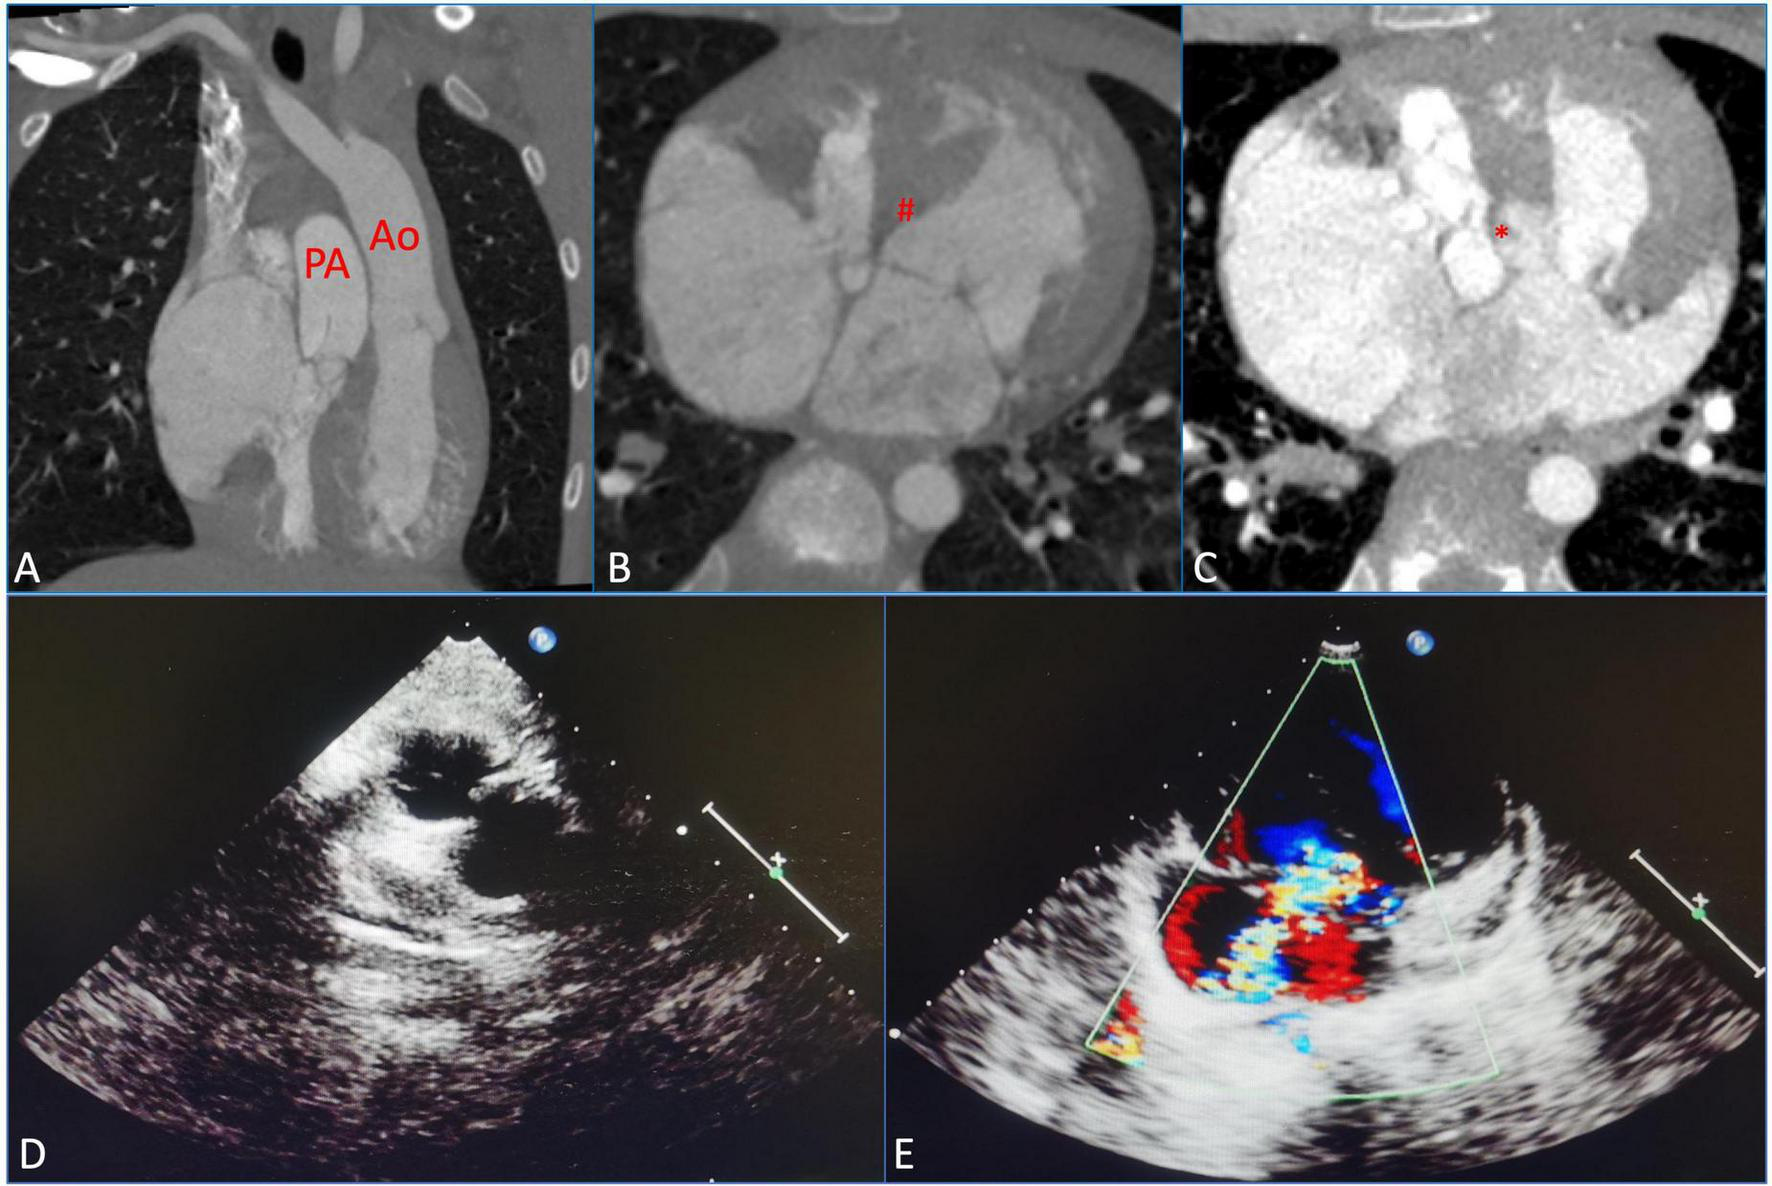

A 10-year-old girl had heart murmurs for 8 years with obvious cyanosis. The oxygen pressure of arterial blood (PO2) was 33.4 mmHg, and the saturation of arterial blood oxygen (SpO2) was decreased to 60.5%. Preoperative computed tomography angiography (CTA) suggested ccTGA, severe PS, and membranous ventricular septal aneurysm (MVSA) (maximum diameter was up to 14 mm) with multiple defects, atrial septal defect (ASD) (the length of ASD was 1.5 cm) (Figures 1A–C). Preoperative echocardiography (ECG) displayed severe PS (the inner diameter of the pulmonary artery was 22 mm) and severe TR (the regurgitation volume was 8.0 mL) (Figures 1D, E). The left ventricular systolic function was normal [left ventricular end-diastolic volume index (LVEDVI) was 47 mL/m2].

FIGURE 1

Preoperative measurements using computed tomography, angiography, and echocardiography were assessed before the surgical repair. (A) Congenitally corrected transposition of the great arteries (ccTGAs). (B) Membranous ventricular septal aneurysm (MVSA). (#) Represents MVSA. (C) Atrial septal defect (ASD). (*) Represents ASD. (D) Severe pulmonary stenosis (PS). (E) Severe tricuspid regurgitation (TR). PA, pulmonary artery; Ao, aorta.